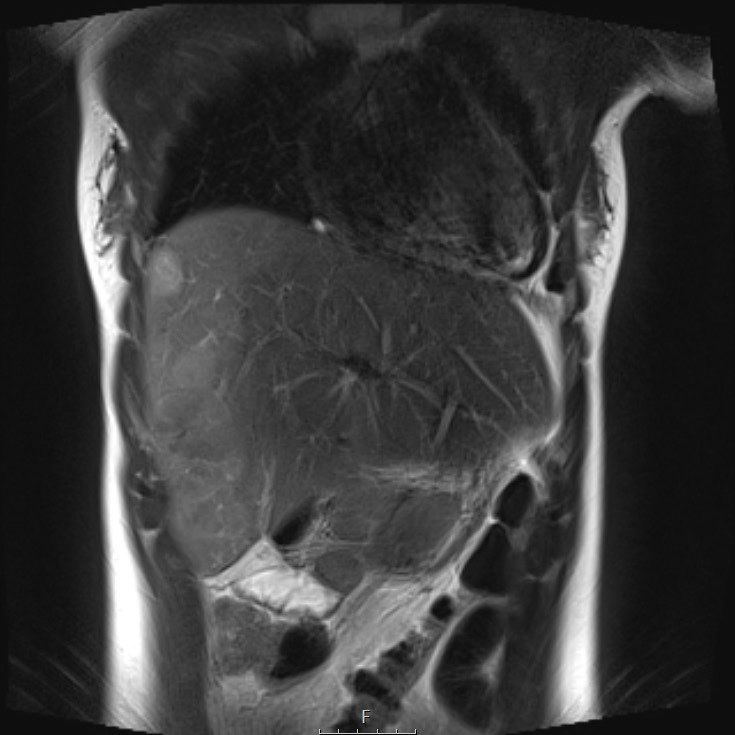

Cuộn qua chuỗi ảnh T2 theo mặt phẳng coronal.

Nghiên cứu các hình ảnh và sau đó tiếp tục đọc.

The findings are:

- Mass with encasement of the aorta and splanchnic vessels.

- Lan rộng dọc theo cột sống ngực nhưng không xâm lấn vào ống sống.

- Small liver metastases.

- Left supraclavicular mass.